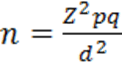

COPD severity was assessed using GOLD guideline. Out of 100 COPD patients, 38% had severe COPD (GOLD stage III). 16 % patients were in mild (Stage I) and 32% patients were in moderate stage (Stage II). The condition was very severe for 14% patients (Stage IV). Of 100 COPD patients. 30% had microalbuminuria. Figure 1

Figure 1.Distribution of COPD patients according to having microalbuminuria (n=100)

Microalbuminuria is an important risk factor for cardiovascular diseases. Microalbuminuria may be seen due to hypoxemia in patients with chronic obstructive pulmonary disease (COPD)22. This study was designed to assess the prevalence of microalbuminuria and its relation with hypoxemia in patients with COPD. Total 100 patients were included. The mean age was 58.16±5.4 years, ranging from 50 to 74 years. This is concordant with the findings of Sujay and Gajanan 23 who found a mean age of 59.67±5.60 years in their study. Majority patients belonged to age group 55 to 60 years (42%), followed by 61 – 65 years (28%). This is slightly different from the findings of Alam et al 24 who reported that majority COPD patients were aged between 60 – 69 years (27.5%) followed by 50 – 59 years (13.6%). This difference may be due to age grouping between the reports. But both the studies confirm that age is a well established risk factor for COPD as increasing prevalence of COPD is noted in higher age groups 79. In this study 82% patients were male and 18% were female. Sujay and Gajanan 23 and Bulcan et al 25 reported a similar high prevalence of male in their study. The high prevalence of male among COPD patients can be linked to high prevalence of tobacco use among male adults in Bangladesh as noted by Khandker et al 26. Majority patients were day labourer (30%), farmer comprised 16% and businessman comprised 16% of study population. Alam et al24 noted that COPD prevalence in Bangladeshi adults were about three times higher in manual workers than non-manual workers. This explains the high prevalence of day labourer and farmers in this study. Slightly more than half of the patients (54%) came from rural area. This was also noted in the study by Alam et al 24 in Bangladesh and Zhong et al 27 in China. Such community variability of COPD can be explained by connecting occupations like farmer living in rural area, use of biomass fuel in the village community and smoking habit among manual workers. Majority patients were illiterate (34%), followed by 26% patients appeared at primary education. This higher prevalence of lower educational qualification in COPD patients was also found in the study by Alam et al24. Majority of the patients came from lower income categories in this study. A similar finding was elicited by Alam et al24 in their study COPD prevalence study among the adult population of Bangladesh. In the present study, 80% of patients were active smokers. Among them, 52% of patients smoked 26 to 35 pack-years. The mean smoking pack-year was 29.62±6.41 years. A similar mean pack-year of 28.91±6.13 was reported by Sujay and Gajanan in their study entitled “Clinical significance of microalbuminuria and hypoxemia in patients with chronic obstructive pulmonary disease” 23. On the other hand Casanova 28 found a high mean pack-year of 58±25 among COPD patients in their study entitled "Microalbuminuria and hypoxemia in patients with chronic obstructive pulmonary disease”. In the present study 38% patients had severe COPD (GOLD stage III), 32% had moderately severe COPD (GOLD stage II), 16% had mild disease (GOLD stage I) and 14% had very severe disease (GOLD stage IV). In contrast Sujay and Gajanan (2) reported 25% GOLD Stage I, 21% Stage II, 20% Stage III, and 34% Stage IV COPD cases in their study. Stage IV cases were higher in their study in comparison to present study. Alam et al (3) in their study entitled “Prevalence and determinants of chronic obstructive pulmonary disease (COPD) in Bangladesh” found that among 13.5% cases of COPD 8% had GOLD stage II disease, 2.7% had stage I disease, 2.3% had stage III disease and 0.6% had Stage IV disease. Their study was community based and depicts the proportion of COPD severity in the community. In contrast the present study as well as the study by Sujay and Gajanan23 was conducted in a hospital setting where advanced cases COPD cases usually get admitted. Microalbuminuria (MAB) was found in 30% patients. This is concordant with other studies: Mehmood and Sofi (8) reported MAB in 20.6% COPD patients and Sujay and Gajanan23 reported MAB in 30% patients. Casanova27 compared presence of MAB in COPD patients and non-COPD smoker controls and found higher prevalence of MAB among COPD patients. In a study by Bulcun et al., 25 it was found that the prevalence of MAB is 39%. In the present study, majority of COPD patients with MAB had GOLD stage of III (40%) and Stage IV (33%), and this association was statistically significant; P = 0.025. In a study by Casanova et al., 28 any association between MAB and spirometric severity of COPD was not observed. Mehmood and Sofi 29 found that COPD patients with MAB had significantly lower levels of FEV1which is similar to finding of present study. In the present study COPD with MAB patients had mean FEV1 % predicted of 37.40±14.48which is significantly lower than those without MAB (59.34±22.78). 26% patients were in hypoxemic status in this study. MAB was significantly more in COPD patients having PaO2 below 70 mm Hg as compared to COPD patients having PaO2 above or equal to 70 mmHg (86.7% vs. 13.3%, respectively, P < 0.001), which indicates COPD patients with MAB were more hypoxemic. In a study by Sujay and Gajanan a Casanova et al. 28 and Mehmood and Sofi, 29 patients with COPD and MAB were more hypoxemic than those without MAB, and it was inversely related to PaO2.